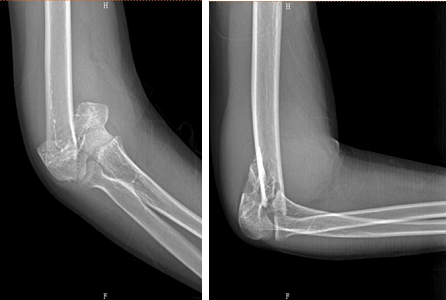

男性,22岁,摔伤致右肱骨髁间骨折

术前

术后